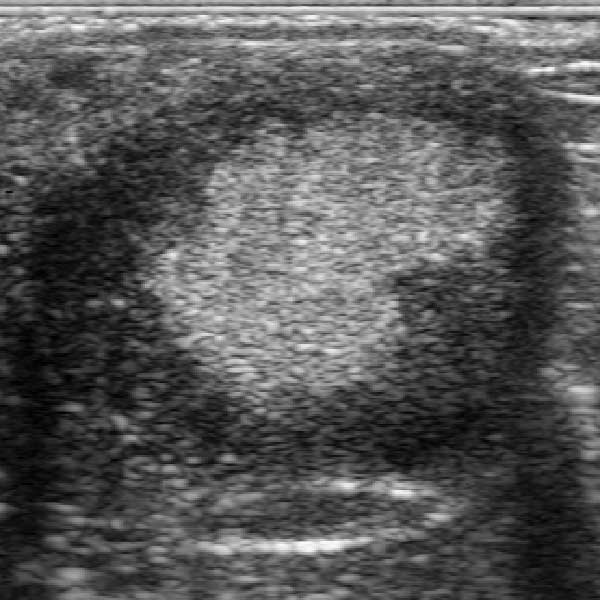

However, conversely sometimes an ‘extra’ CL was seen , not corresponding to the number seen post-ovulation. At 21 days the new CL was obvious from its appearance, to be a late dioestrus ovulation from a follicle often identified at the 12-15 day examination. The new CL and the CL verum were then seen and recorded at all subsequent examinations. At 35-45 days one or more large follicles were commonly found some of which were seen to ovulate, mostly at about 38-45 days. By 50 days the ovaries could then contain up as many as 5 CLs, e.g. one or two CL vera, one dioestrus and one or two secondary CLs from 40+ day ovulations. In contrast the pregnancy may still be supported by a single CL verum. From 65 days onwards, due to circulating equine Chorionic Gonadotrophin, new follicles began to develop and to subsequently luteinise and were recognised as luteinised unruptured follicles (LUF). As they mature, LF become increasingly similar to normal mature CL. Repeated examinations at this time recognised the appearance of any new CL or LUF in addition to the CL verum and any CL from earlier dioestrus ovulations. In this study from recording the number of luteal structures (LS) in each ovary, it was possible to correlate this with any earlier data from the same mare.

Although early dioestrous ovulations were in minority, many mares ovulated at around 38-45 days. However there were instances of mares in which there were no dioestrous ovulation (no extras CL), no accessory CL from 40 day ovulations and no subsequent luteinised follicles. It was apparent that in these cases, no ovulatory size follicle and often not even relatively small follicles were recorded. The ovaries had ceased to develop new follicles so that it was not possible for any ovulation or luteinisation. Yet the pregnancies continued to develop normally, maintained in some cases by a single corpus luteum verum. Although blood samples were not taken, since few of these pregnancies failed, it is reasonable to assume that endometrial cups developed and eCG was secreted.